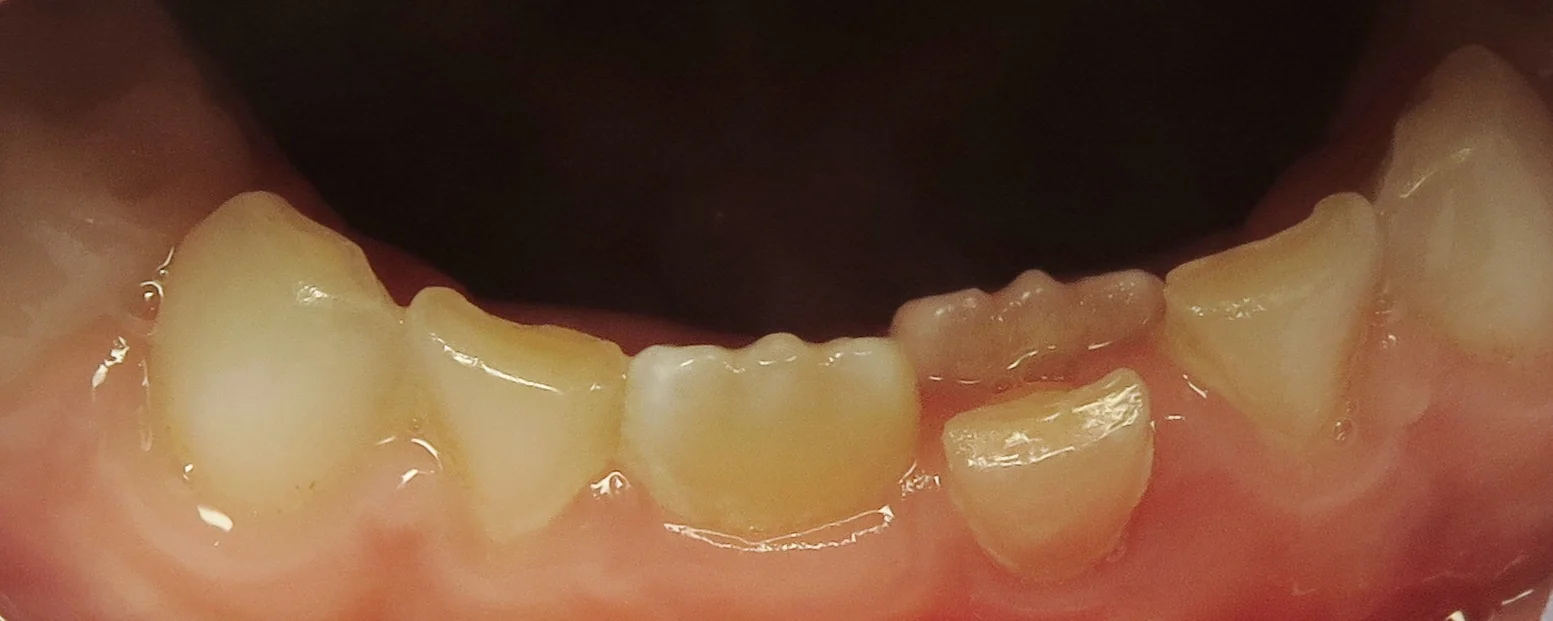

Dr. Kari's son Duke with his two mandibular primary central incisors erupting. These are usually the first teeth to appear.

Likewise, the mandibular primary central incisors are the first baby teeth to be lost (notice the permanent tooth erupting it its place).

Retained teeth are usually a problem localized to the mandibular and maxillary incisors (four front teeth). The two mandibular primary central incisors are the first teeth to erupt at about six months. Subsequently, they are the first baby teeth lost at five to six years. They make way for the mandibular permanent central incisors, which typically erupt at ages six to seven. You can definitely see how a small overlap in timing can create the "double tooth" problem.